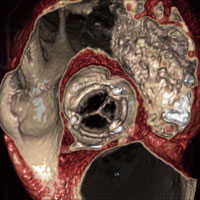

さらに,今回は“PhyZiodynamic inVivo”という,最新の技術が参考出品された。inVivoでは,PhyZiodynamicsの処理画像を含めてさまざまなモダリティデータを合成し,4Dで画像処理を行うことが可能である。1万8000スライスの画像を,速度を落とさずにリアルタイムに処理できる。それによって,心臓や脳の内部の動きがリアルに観察でき,従来には考えられなかった知見が得られるという。デモコーナーでは,心臓の弁のスムーズな動きや,頭部領域で血流とパフュージョンのデータを重ね合わせた4D や,4DによるSPECT/CTなど,今まで見ることができなかったリアルな生体画像が紹介されていた。

心臓の弁の動きをなめらかに表示

4D心臓フュージョン